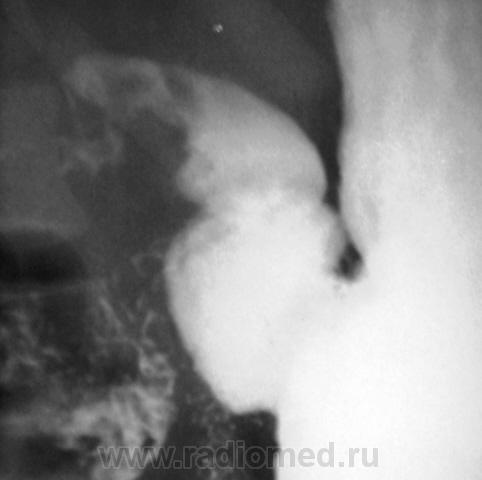

Примерно так....

...и другой пример, на "рельефе"...см. просто снимок и схему по снимку....